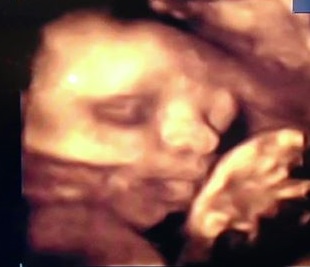

Méretek, UH képek

Első trimeszter

Az első 12 hét

29. HÉT

29. hét 3. nap

29. hét 5. nap